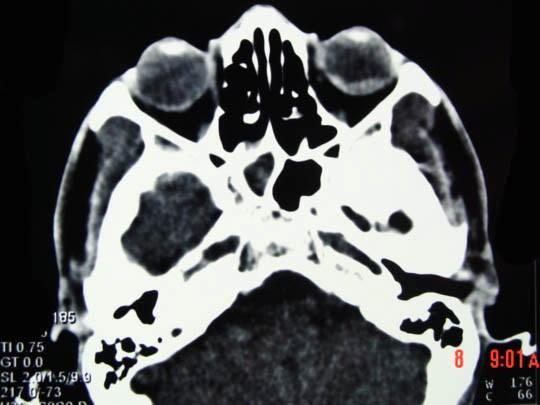

问题 男,37岁,近半年来视力下降明显,近一个月失明,CT如图所示,最可能的诊断为 ( )

选项 A、色素膜神经瘤伴视网膜脱离 B、黑色素细胞瘤伴视网膜脱离 C、色素膜血管瘤伴视网膜脱离 D、色素膜转移瘤伴视网膜脱离 E、色素膜黑色素瘤伴视网膜脱离

答案 E